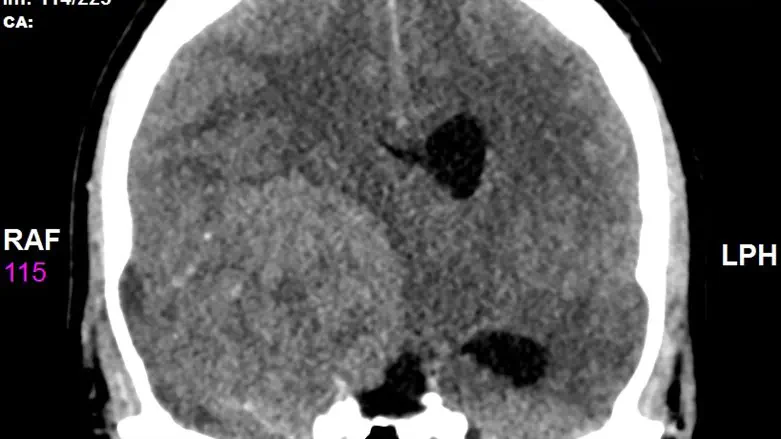

הצילום לא הותיר כל ספק: הצעיר סובל מגידול ענק מימדים בראשו וזה מה שיוצר את הלחץ הבלתי נסבל עד כדי איבוד הכרה. “לרגעים אחדים היה נראה לנו שאנו מאבדים אותו חלילה ונערכנו לכל תרחיש שיתפתח”, אומר ד”ר נבו מרגלית.

ואכן, הצעיר הובהל לניתוח דחוף, במהלכו הוצא מראשו גידול ענק “בגודל של אשכולית”, וכעבור מספר שעות בחדר התאוששות התעורר והחל לתקשר עם סובביו.